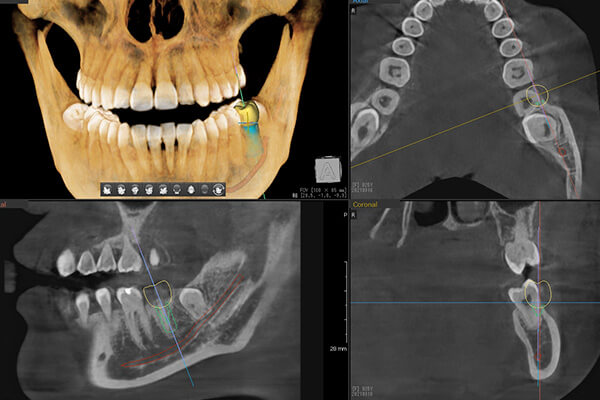

歯科用CTを活用した精密診断

インプラント治療で大切なのは、骨や血管・神経の位置関係を正確に診断することです。そこで当院では3次元的な画像を撮影できる最新型のCTを導入しています。被ばく量が少なく、撮影時間も短いです。CT検査では、撮影した画像を元にシミュレーションを実施でき、上顎洞や顎の中の神経を避けて外科処置ができるのです。